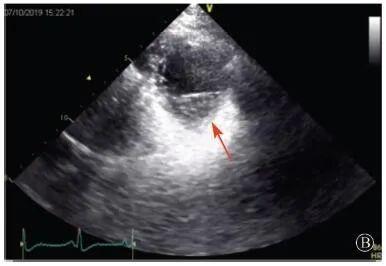

患者入院后無(wú)特殊不適,心率70次/min,血壓110/60 mmHg,心功能Ⅱ級(jí)。查血常規(guī):血紅蛋白139 g/L,白細(xì)胞7.39×109/L,血小板221×109/L。尿常規(guī)、便常規(guī)+潛血均正常。生化:丙氨酸氨基轉(zhuǎn)移酶38 U/L,白蛋白47 g/L,鉀3.9 mmol/L,肌酐(酶法)65 μmol/L,總膽固醇3.52 mmol/L,低密度脂蛋白膽固醇2.08 mmol/L。CK:1256→487 U/L,CK-MB 9.7→3.8 μg/L,cTnI 85.90→68.50 pg/ml。N末端B型利鈉肽原70 pg/ml。CK同工酶電泳:肌酸激酶MM質(zhì)量100.0%(此時(shí)CK-MB已正常)。血沉1 mm/第1小時(shí),高敏C反應(yīng)蛋白1.61 mg/L;補(bǔ)體:C3 0.876 g/L,C4 0.174 g/L。免疫球蛋白:IgG 9.52 g/L,IgA 1.73 g/L,IgM 0.62 g/L。血清蛋白電泳未見(jiàn)M蛋白。糖化血紅蛋白5.1%。乳酸(運(yùn)動(dòng)前)1.1 mmol/L,乳酸(運(yùn)動(dòng)中)6.6 mmol/L,乳酸(運(yùn)動(dòng)后)7.8 mmol/L。肌炎抗體譜:抗PM-SCL75(+),余均(-)。心電圖:aVL、V5、V6導(dǎo)聯(lián)T波倒置(圖2)。冠狀動(dòng)脈CT未見(jiàn)明顯異常。超聲心動(dòng)圖:左室舒張末內(nèi)徑55 mm,左室收縮功能減低,心尖部、左室壁普遍運(yùn)動(dòng)減低,以左室下后壁為著,左室下后壁肌小梁明顯增多可見(jiàn)隱窩,疏松層與致密層之比為1.7;左室射血分?jǐn)?shù)(雙平面)45%;右冠狀動(dòng)脈開(kāi)口6.5 mm,開(kāi)口處未見(jiàn)明確瘤樣擴(kuò)張(圖3)。

協(xié)和疑難︱第67例:臨床表現(xiàn)胸痛伴肌酸激酶升高

A:胸骨旁長(zhǎng)軸平面,左室舒張末內(nèi)徑略增大,室壁無(wú)明顯增厚;

B:胸骨旁左室短軸切面心尖水平,可見(jiàn)心肌肌小梁增多,其內(nèi)可見(jiàn)隱窩(箭頭所示)

圖3 患者入院后超聲心動(dòng)圖